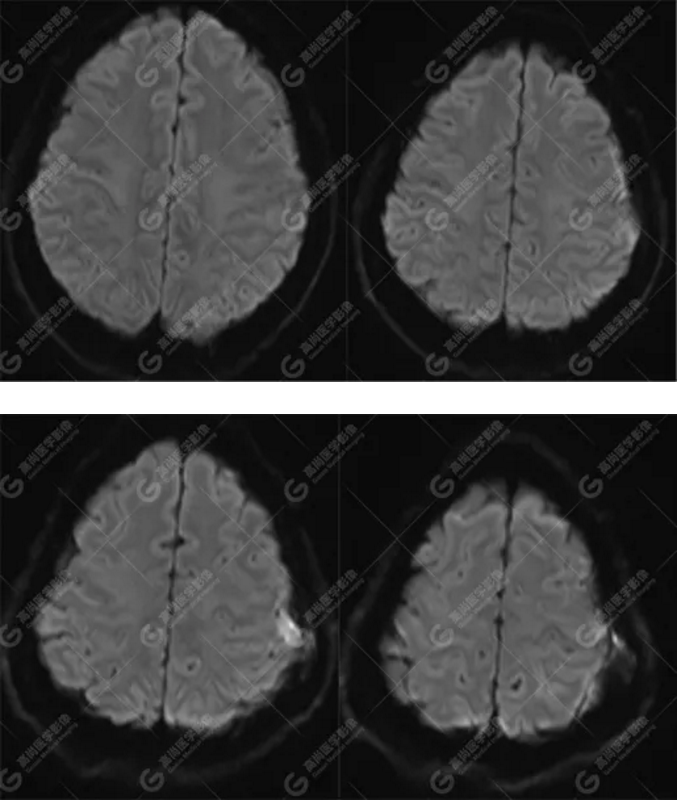

MR圖像

左側額頂部顱骨骨質破壞并相鄰硬腦膜增厚強化,考慮Rosai Dorfman?。≧DD)可能,需與朗格漢斯細胞組織細胞增生癥鑒別。

總之,顱內RDD是一種罕見的硬腦膜良性病變,若 MRI發(fā)現(xiàn)顱內基于硬腦膜扁平或匍匐生長的孤立或者多發(fā)腫塊,CT 檢查未見鈣化,而MR檢查T2WI及 DWI呈低信號,增強明顯均勻強化,應考慮到 RDD 的可能。